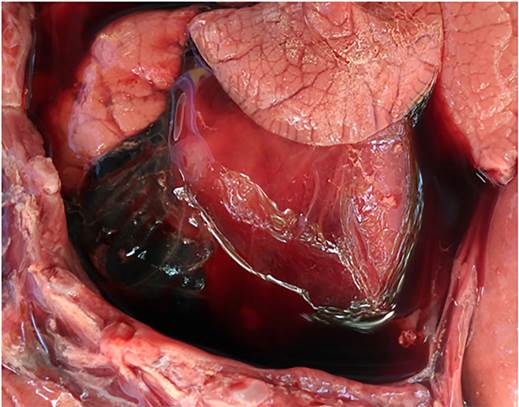

All five necropsied fetuses (cases 1-5) had approximate gestational ages of 180 d. Grossly, case 1 had diffuse fibrinous epicarditis (Figure 1) and peritonitis. Histologically in this fetus, there was neutrophilic bronchopneumonia and epicarditis. Campylobacter fetus was detected by direct immunofluorescence and isolated from abomasal fluid and lung. Identification of the isolate was further confirmed by PCR, which yielded amplification products of sizes corresponding to those described for C. fetus subsp. venerealis11,12. Additionally, the 16S rDNA gene sequence of the isolates was compatible with C. fetus. No Campylobacter spp. were isolated from samples of cases 2-5.

Figure 1 Case 1, aborted by Campylobacter fetus subsp. venerealis. The epicardium is covered by moderate to large amount of fibrinous material along with serosanguinous fluid